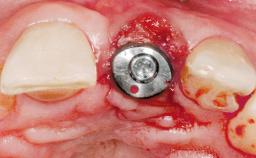

A 30-year-old female patient had lost tooth 21 and was referred to our clinic for consultation and treatment. Due to advanced apical infection, tooth 21 had been extracted two months earlier at another clinic and an acrylic-resin tooth had been bonded to the adjacent teeth. The patient desired implant treatment to avoid any damage to the adjacent natural teeth. While the patient had no history of any systemic disorder, she was a heavy smoker and exhibited medium to advanced periodontitis in the entire jaw. After the initial treatment to achieve a pocket probing depth of less than 4 mm and no bleeding on probing, a decrease in the height of the papillae mesial and distal to the extraction site and overall gingival recession were observed.

| Bone Augmentation | Horizontal|Staged |

| Augmentation Materials | Autogenous chips|Membrane |

| Bone Volume | Deficient horizontally, requiring prior grafting |